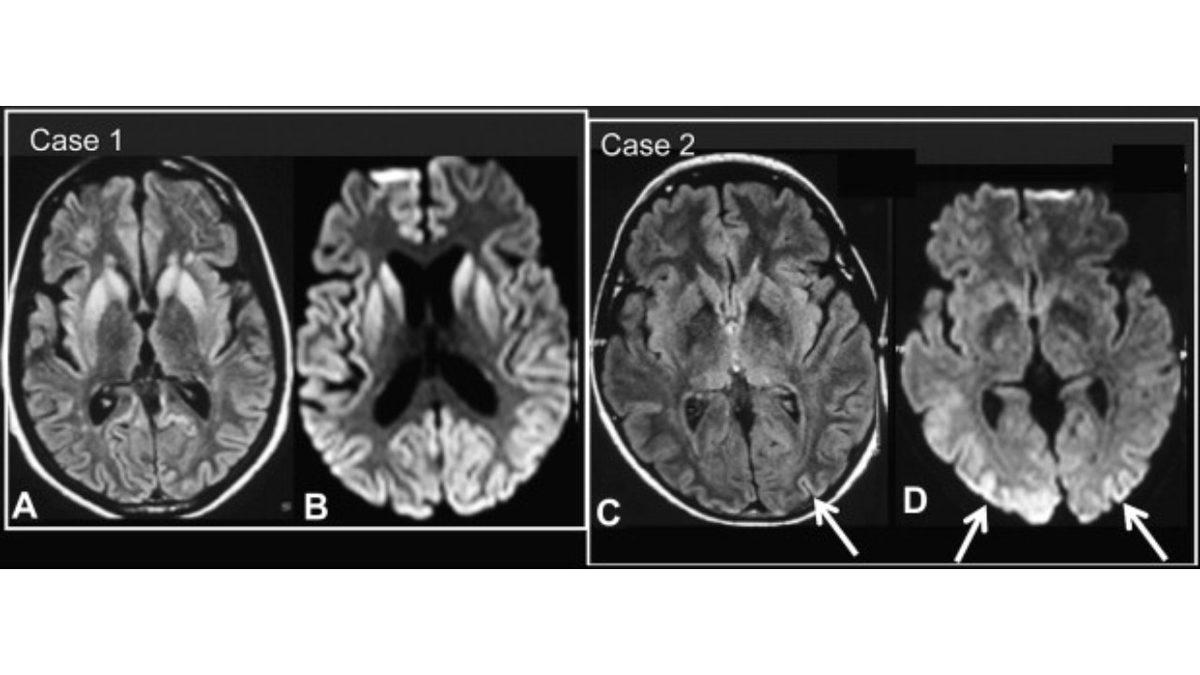

Öte yandan bu rahatsızlığa, beyindeki prionlar yani anormal proteinler sebep oluyor. Bu proteinler de dokularda ne yazık ki geri döndürülmesi imkânsız hasarları beraberinde getiriyor.

Aynı zamanda beynindeki çoğu nöronun düzgün çalışmamasına ve ölmesine sebep olan sünger benzeri delikleri yaratıyor.